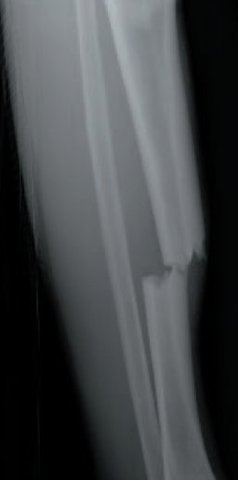

• Bob broke his leg

Bob broke his leg

Bob was riding his bike and fell

• Bob Went To The Hostpital

Bob Went To The Hostpital

His parnts to him to the hostpital and they said his let was brokin.